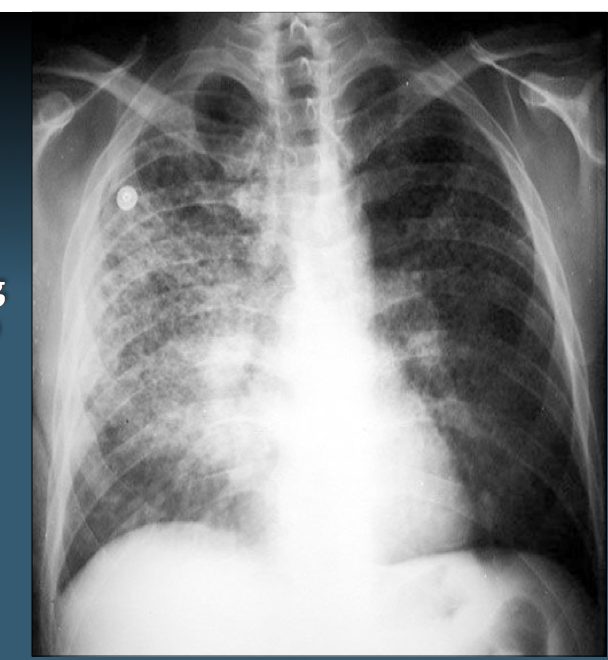

The following are hallmarks of which dz?

Hypoxemia & bilateral radiographic opacities

Acute Respiratory Distress syndrome (ARDS)

(note- this is NOT the same as respiratory distress syndrome in newborns)

What is the most common CXR finding in interstitial lung dz

Reticular “netlike” opacities

**this will be on exam**